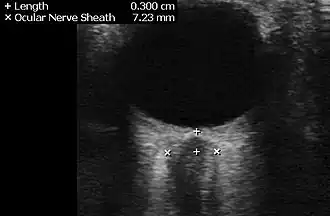

- ^ "UOTW #5 - Ultrasound of the Week". Ultrasound of the Week. 17 June 2014. Retrieved 27 May 2017.